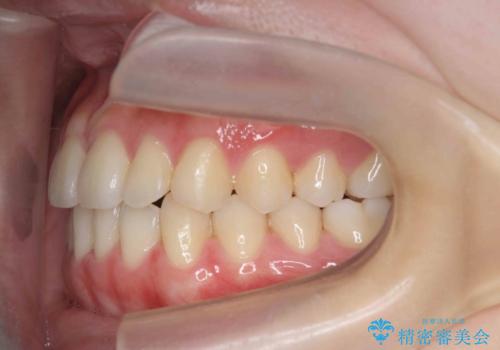

ガタつきの改善 マウスピース矯正治療

- 歯のがたつきの改善を求めて、矯正治療を希望され来院されました。

少量の歯のディスキング、歯列弓拡大、アタッチメントを装着することで審美的な歯列へとマウスピース矯正インビザラインを用いて治療を行います。

マウスピース矯正は装着時間の遵守が非常に大切ですが、しっかりと20時間/日以上の装着を守っていただいたおかげで良好な治療結果を得ることができました。